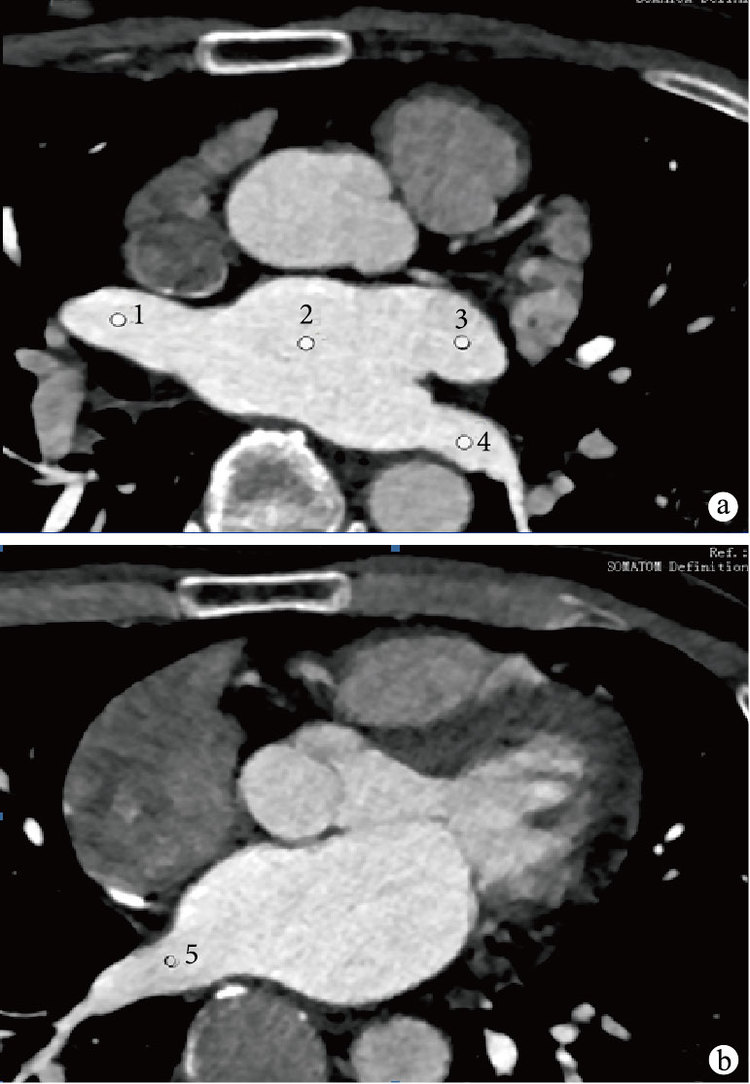

將掃描采集的原始數據傳輸至隨機工作站的Viewing軟件中,并將其重建為層厚3 mm、層間距3 mm的最大密度投影(MIP)圖像,算法為B31f medium。分別對患者的左心房、左上肺靜脈、左下肺靜脈、右上肺靜脈、右下肺靜脈進行測量(圖 1)。上述5個層面中,對每層圖像又分別取其中心層面及上下層面各3層,以像素50 mm2大小的圓形興趣區,測量左心房、肺靜脈CT值及圖像噪聲值,即在每一層上取左心房及左上、左下、右上、右下肺靜脈的平均值,將上、中、下3層面的平均值作為該層面圖像的CT值及圖像噪聲值。然后測量相同層面上背脊肌的CT值(E),計算CT值的標準差值(SD值)。按照公式對比噪聲比(CNR)=(感興趣區CT值?E)/SD,分別計算左心房-背脊肌、左上肺靜脈-背脊肌、左下肺靜脈-背脊肌、右上肺靜脈-背脊肌、右下肺靜脈-背脊肌的CNR,按照公式信噪比(SNR)=感興趣區CT值/SD,分別計算左心房及左上、左下、右上、右下肺靜脈SNR。